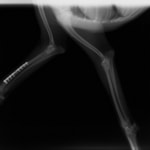

ペルシャ猫 11ヶ月齢 雄

他院にて左大腿骨遠位の成長板骨折(salter-harrisⅠ型)が認められており、治療相談を目的として来院。当院にて、キルシュナーワイヤーを用いたピンニングにより骨折部位の整復を行いました。術後の経過は良好で、現在も経過観察中です。

術前レントゲン

術後レントゲン